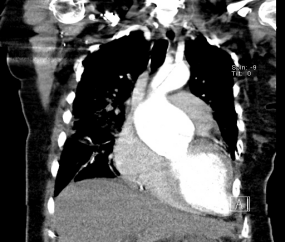

随后急诊医师对患者进行了CTA检查,结果CTA证实患者是主动脉A型夹层,后经及时抢救患者目前已成功手术。

▲CTA:主动脉A型夹层